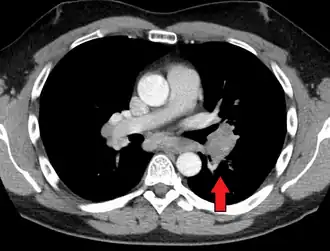

-

Hilar adenopathy especially on the person's left (AP CXR) -

Hilar adenopathy especially on the person's left (lateral CXR) -

Hilar adenopathy especially on the person's left (coronal CT) -

Hilar adenopathy especially on the person's left (transverse CT)